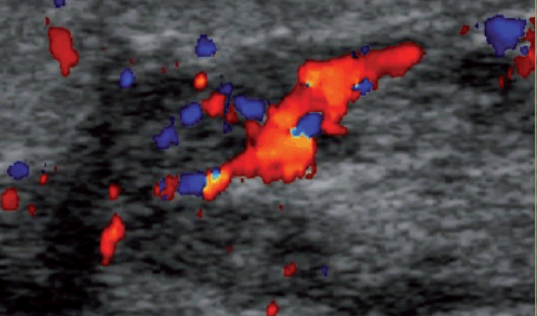

It’s difficult to sleep when the results of a breast cancer recurrence ultrasound are just floating around in the ether. Then going down the google rabbit hole at 2 a.m. is no bueno. Why did I look at the screen when she was performing the ultrasound?? I’m not a radiologist but I guess I’ve seen so many done on both breasts since I’ve had cancer in each that I think I know what to look for but that’s not really true, not a good idea. I saw the doppler show vascularity in the area where I had lymph node involvement and in all the scar tissue that’s grown back after radiation. Blue pulsating and smatterings of red. Which incidentally that scar tissue is causing a capsular contracture, it’s so painful. In the last few months it’s gotten worse, I can’t sleep comfortably on the latest breast cancer side where that scar tissue is and I’ve read that recurrence can happen in those areas. I’m not afraid, that’s not keeping me up at night, it’s just the unknown I guess. Isn’t everything though really unknown until it happens though? What’s the worst that can happen? What’s the best case scenario?